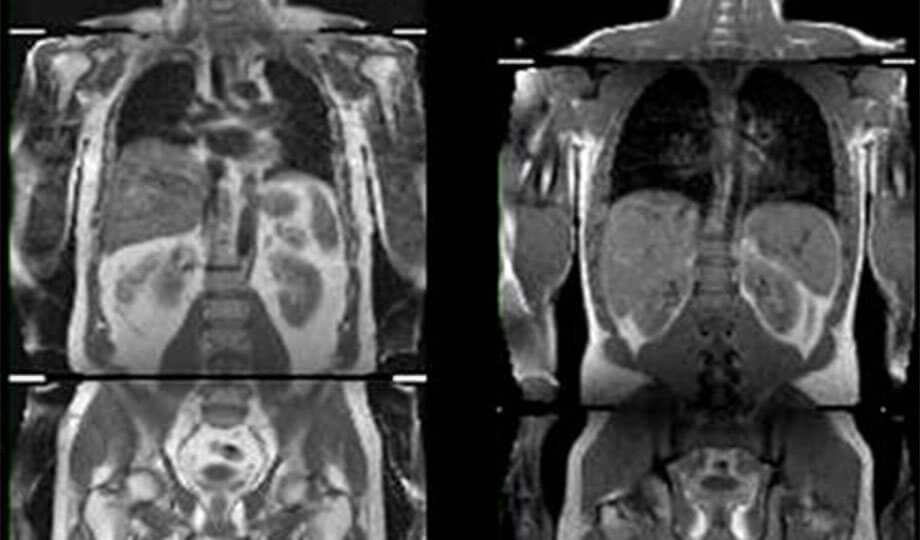

Ученые изучали данные из английского биобанка, собранные у более 500 000 человек возрастом от 37 до 73 лет. МРТ-сканирование талий этих людей показало, где они хранят избыточный жир, и позволило провести параллели с признаками диабетам 2 типа, сердечных приступов и рисков инсульта.

Они нашли 14 генетических вариаций или изменений в молекуле ДНК, связанных с более высоким ИМТ (индекс массы тела), но более низким риском развития диабета, снижения артериального давления и риска сердечно-сосудистых заболеваний. Получается, когда люди набирают вес, имея эти генетические факторы, они хранят избыточный жир под кожей и меньше жира накапливается в основных органах, таких как печень, поджелудочная железа и почки.